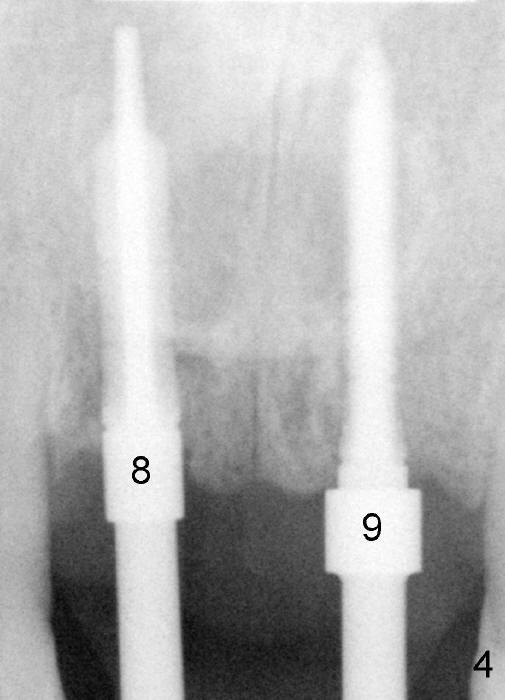

Trajectory is being corrected while osteotomy is increasing with reamers (Fig.4: 3 and 2.5 mm). When a 4.5x20 mm tap is inserted at the site of #8 (Fig.5), it is stable. A 3.5x20 mm tapered drill is at the site of #9 for parallelism. When the tap is removed from the osteotomy of #8, the middle portion of the 3.5x20 mm drill at the site of #9 is seen to pass the socket of the left mesiodens (Fig.6: <).